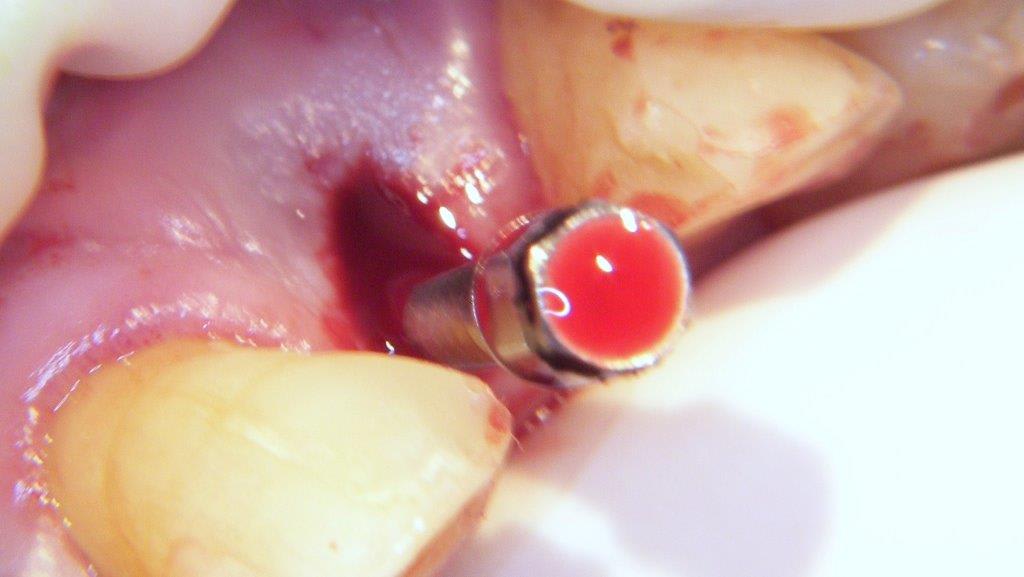

pour ceux que ça intéressent, une petite utilisation d'expansion de la paroi palatine, sur une avulsion d’incisive(racine fendue). toutes mes excuses pour la mauvaise qualité des photos.